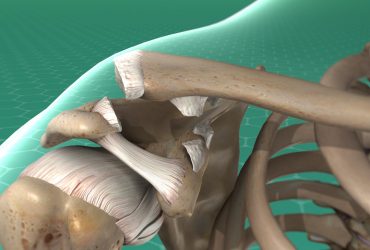

Η χειρουργική επέμβαση σαρκώματος απαιτεί από τους χειρουργούς να αφαιρέσουν όλο το οστό που έχει προσβληθεί από τον όγκο και ένα περιθώριο (όριο) υγιούς ιστού γύρω από τον όγκο. Στη συνέχεια, οι ορθοπεδικοί χειρουργοί μπορούν να ανακατασκευάσουν το οστό, την άρθρωση ή την περιοχή των μαλακών ιστών.

Συνήθως, υπάρχουν αρκετές επιλογές για την αποκατάσταση που μπορεί να χρησιμοποιούν οστικά μοσχεύματα, τεχνητές αρθρώσεις ή συνδυασμό και των δύο. Στόχος είναι η αποκατάσταση του μέρους του σώματος, ώστε ο ασθενής να μπορεί να συμμετέχει στις καθημερινές του δραστηριότητες.